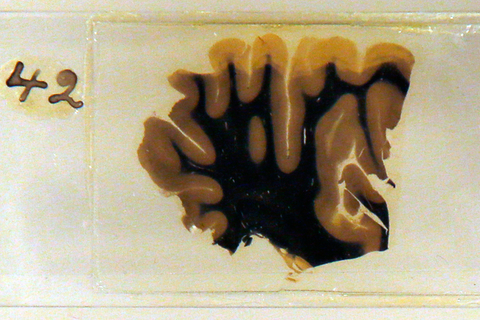

英国“人脑展”展出爱因斯坦大脑切片

2012年3月27日,英国伦敦韦尔科姆收藏馆举办“人脑”展,展品包括部分爱因斯坦的大脑、有300年历史的头盖骨、古埃及的木乃伊大脑,以及存放在广口瓶内的大脑。

01 爱因斯坦大脑切片,保存在甲醛溶液中。 Chris Helgren/REUTERS

02 爱因斯坦大脑切片(右下)和模型。 东方IC